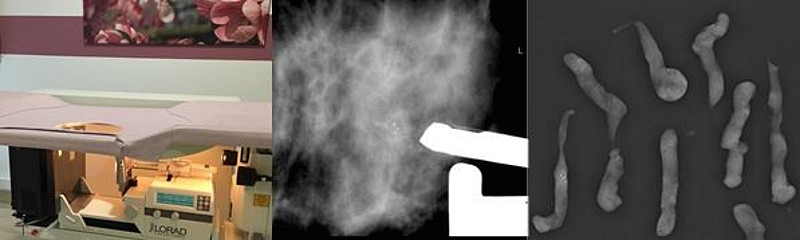

Sie liegen dafür in Bauchlage auf einer Liegevorrichtung mit Mammographie-Gerät (Abb. unten links). Der zu untersuchende Bereich der Brust wird leicht komprimiert. Mittels Mammographie-Aufnahmen der auffälligen Region werden die Veränderungen in der Brust aufgesucht und die Biopsie am Computer geplant. Nach gründlicher Desinfektion der Haut und lokaler Betäubung wird die Biopsienadel computergestützt platziert. Anschließend werden Gewebeproben zielgenau entnommen (Abb. unten Mitte). Die Entnahmestelle wird mit einem kleinen Metallclip (Titanclip) markiert. Im Falle von abklärungsbedürftigen Mikroverkalkungen erfolgt unmittelbar nach der Biopsie eine Röntgenkontrolle der entnommenen Proben um nachzuweisen, dass eine relevante Menge Kalk entfernt wurde (Abb. unten rechts). Der Eingriff dauert ca. 30 Minuten. Nach einer Beobachtungszeit von ca. 60 Minuten wird eine Kontrollmammographie angefertigt und ein Kompressionsverband angelegt, danach können Sie nach Hause gehen. Die entnommenen Gewebeproben werden im Institut für Pathologie des Universitätsklinikums Düsseldorf untersucht.